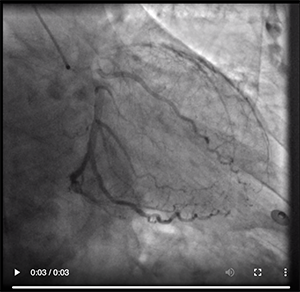

Revascularization seemed appropriate when considering the acute coronary syndrome complicated by VT at presentation, which was probably induced by a large ischemic area. Furthermore, because of his advanced age and high EuroSCORE, we decided to perform percutaneous coronary revascularization of the LM bifurcation lesion (Video 1A, Video 1B). We believed that treating only the LM-LAD would have resulted in worsening of the ostial left circumflex artery, which could cause further ischemia and/or infarction with the risk of VT and/or further reduction of LVEF.

Video 1. Right anterior oblique (A) and spider projections (B) of the LM bifurcation.